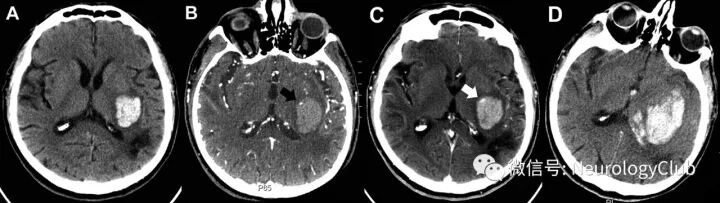

岛征

李琦等于2017年提出,其特征为CT平扫脑出血血肿周围的多灶性小出血。需满足以下两个标准中的任一条件即可定义:(1)存在≥3个分散小血肿全部与主要血肿分离或(2)存在≥4个小血肿,部分或全部与主要血肿相连。分散的小血肿好似分离的小岛,可以是圆形或椭圆形,与主要血肿分开。岛征预测ICH患者早期血肿扩大的敏感性、特异性、阳性预测值及阴性预测值分别为44.7%、98.2%、92.7%及77.7%。主要的血肿由破裂的血管出血引起,当该血肿在不断扩大时,可能导致邻近的小动脉损害,从而引起血肿周围出现海岛样不规则小血肿。岛征具有很高的特异性,可提示血肿扩大,其出现也意味着脑出血患者预后不良。在一些文献上也称主要血肿周围的小出血灶为“卫星征(satellite sign)”,其定义:CT平扫≥1个平面上邻近但与主要血肿分离的小出血(最大直径<10mm),卫星灶和主要血肿的最短距离为1-20mm。有学者研究认为其对预测血肿扩大及预后不良也有价值。

(图7:脑出血岛征)

(图8:a-c:脑出血卫星征;d:脑出血未见卫星征;注意其与岛征定义上的不同)